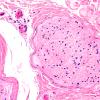

1A1 CMT 1A (PMP22 dup Case 1) H&E 20X

1A2 (Case 1) H&E 40X 12